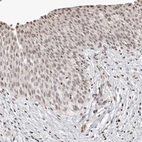

Immunohistochemical staining of human lung shows strong cytoplasmic-nucleus positivity in macrophages.